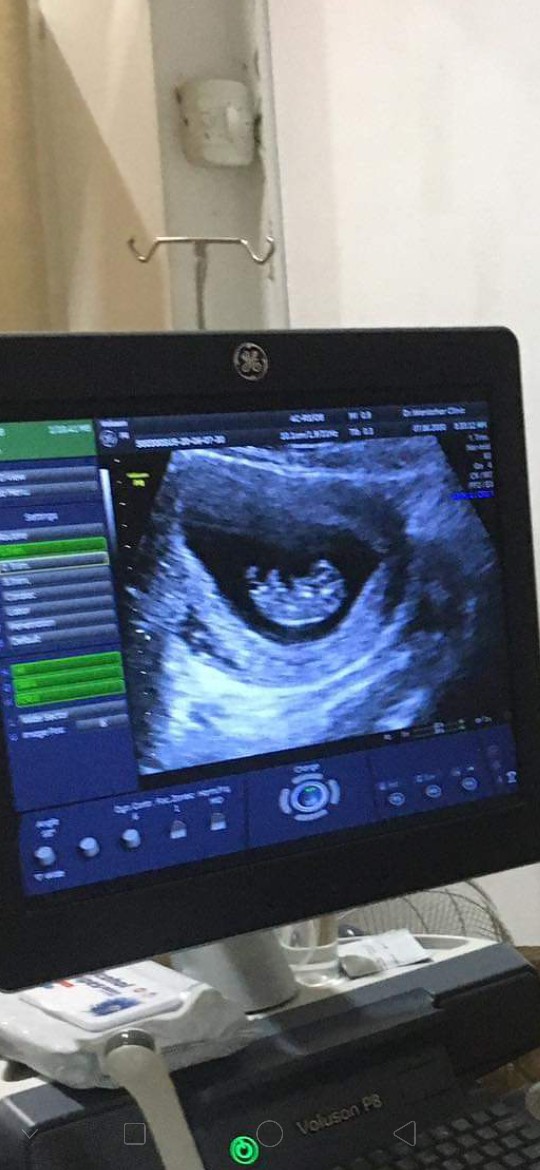

ของเรา9สัปดาห์จ้า